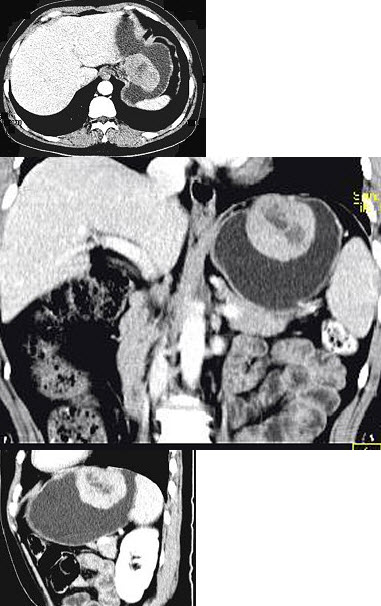

女,51岁,上腹部隐痛不适,CT检查如图,可能的诊断是( )

A:胃癌

B:胃息肉

C:胃腺瘤

D:胃溃疡

E:胃间质瘤